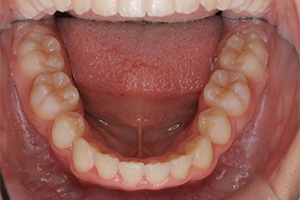

矯正治療のCASE 06

Before

After

-

- 主訴

- 口元が出ているのが気になる

- 治療内容

- ラビアル矯正(表側)

抜歯あり

- 治療費用

- 88万円~(税込)

- 治療期間

- 20か月

【リスク・副作用】

歯の痛み、口内炎、歯磨きがしにくいことによるむし歯や歯周病のリスク、歯根吸収や歯の変色、後戻りなどの副作用があります。